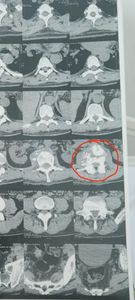

Em 31 de dez de 23, tive um desmaio na de véspera de réveillon onde eu fraturei a coluna. E de lá para cá eu tive mais dois desmaios, uma sequência de crise de pânico devido ao trauma, e um dia tive crise dirigindo, fui socorrido por amigos e familiares, onde eu perdi completamente o sentido cheguei até a pensar que estava perdendo a faculdades mentais. Em janeiro comecei a investigar e descobri que estava com a fratura na coluna através de uma tomografia conforme imagens anexas, que fui ajudado por um anjo da guarda pois eu não tinha um centavo naquele momento. O negócio local tinha parado, eu não estava conseguindo fazer as refeições (marmitas), pois não conseguia ficar em pé.